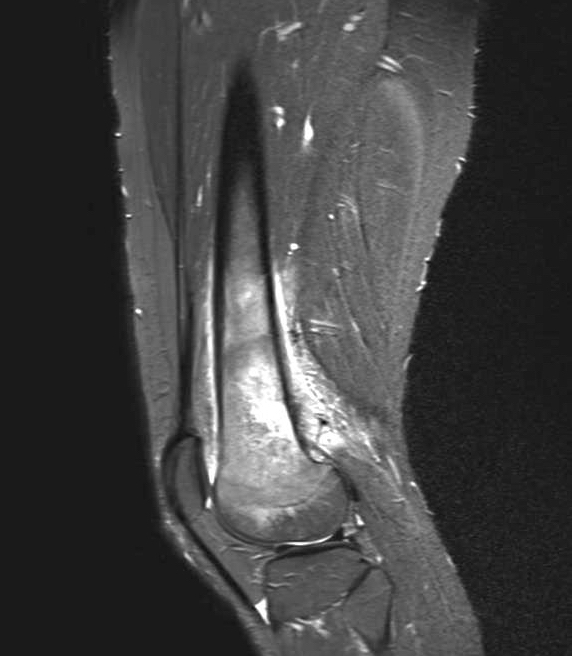

- Conventional central osteosarcoma (Radiographics 2010;30:1653):

- Medullary and cortical bone destruction

- Wide zone of transition, permeative appearance

- Aggressive periosteal reaction

- Sunburst type

- Codman triangle

- Lamellated (onion skin) reaction

- Tumor matrix ossification / calcification

- Soft tissue involvement

Radiology images